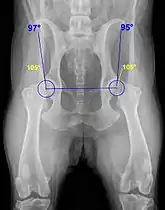

Apesar de geralmente ser um cão rústico, exemplares da raça rottweiler podem ser acometidos com maior frequência por três principais problemas de saúde: infecções que afetam o sistema gastro intestinal (á exemplo da parvovirose), principalmente quando bem jovens; câncer ósseo; e displasia coxofemoral, que é uma doença ortopédica de cunho hereditário.[15][16]

As infecções que afetam o sistema gastro intestinal e a displasia coxofemoral podem ser precavidas, com um bom esquema vacinal e sanitário no caso do parvovírus; e com controle radiológico de reprodutores no caso da displasia coxofemoral.[15][16]